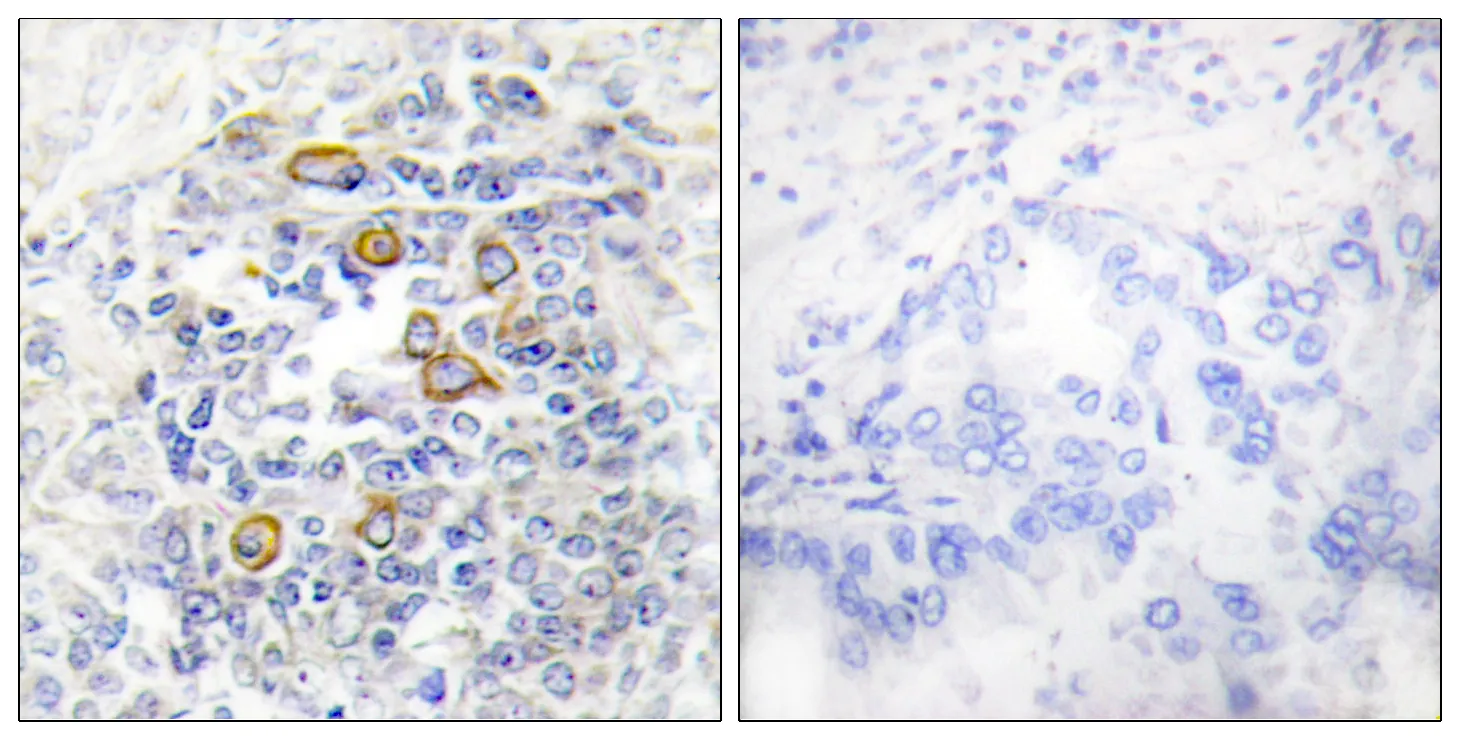

MDM2 Rabbit Polyclonal Antibody

Cat: APRab13758

Size1:50μl Price1:$118

Size2:100μl Price2:$220

Size3:500μl Price3:$980

Size2:100μl Price2:$220

Size3:500μl Price3:$980